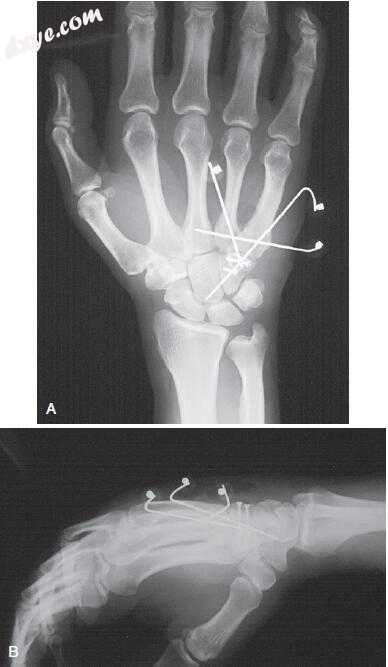

47.jpg

图.47  A,舟骨,跨头状骨骨折脱位最好通过背侧方法稳定。 采用两个无头空心螺钉固定骨折,并用近端 - 远端方向插入的单个螺钉固定舟骨骨折。 患者完全撕裂了月三角骨间韧带; 它主要是用克氏针进行修复和提供稳定的,最终将其克服。 B,横切开放复位内固定后,经跨头状骨骨折脱位。 X光片证实了舟月角的恢复正常。